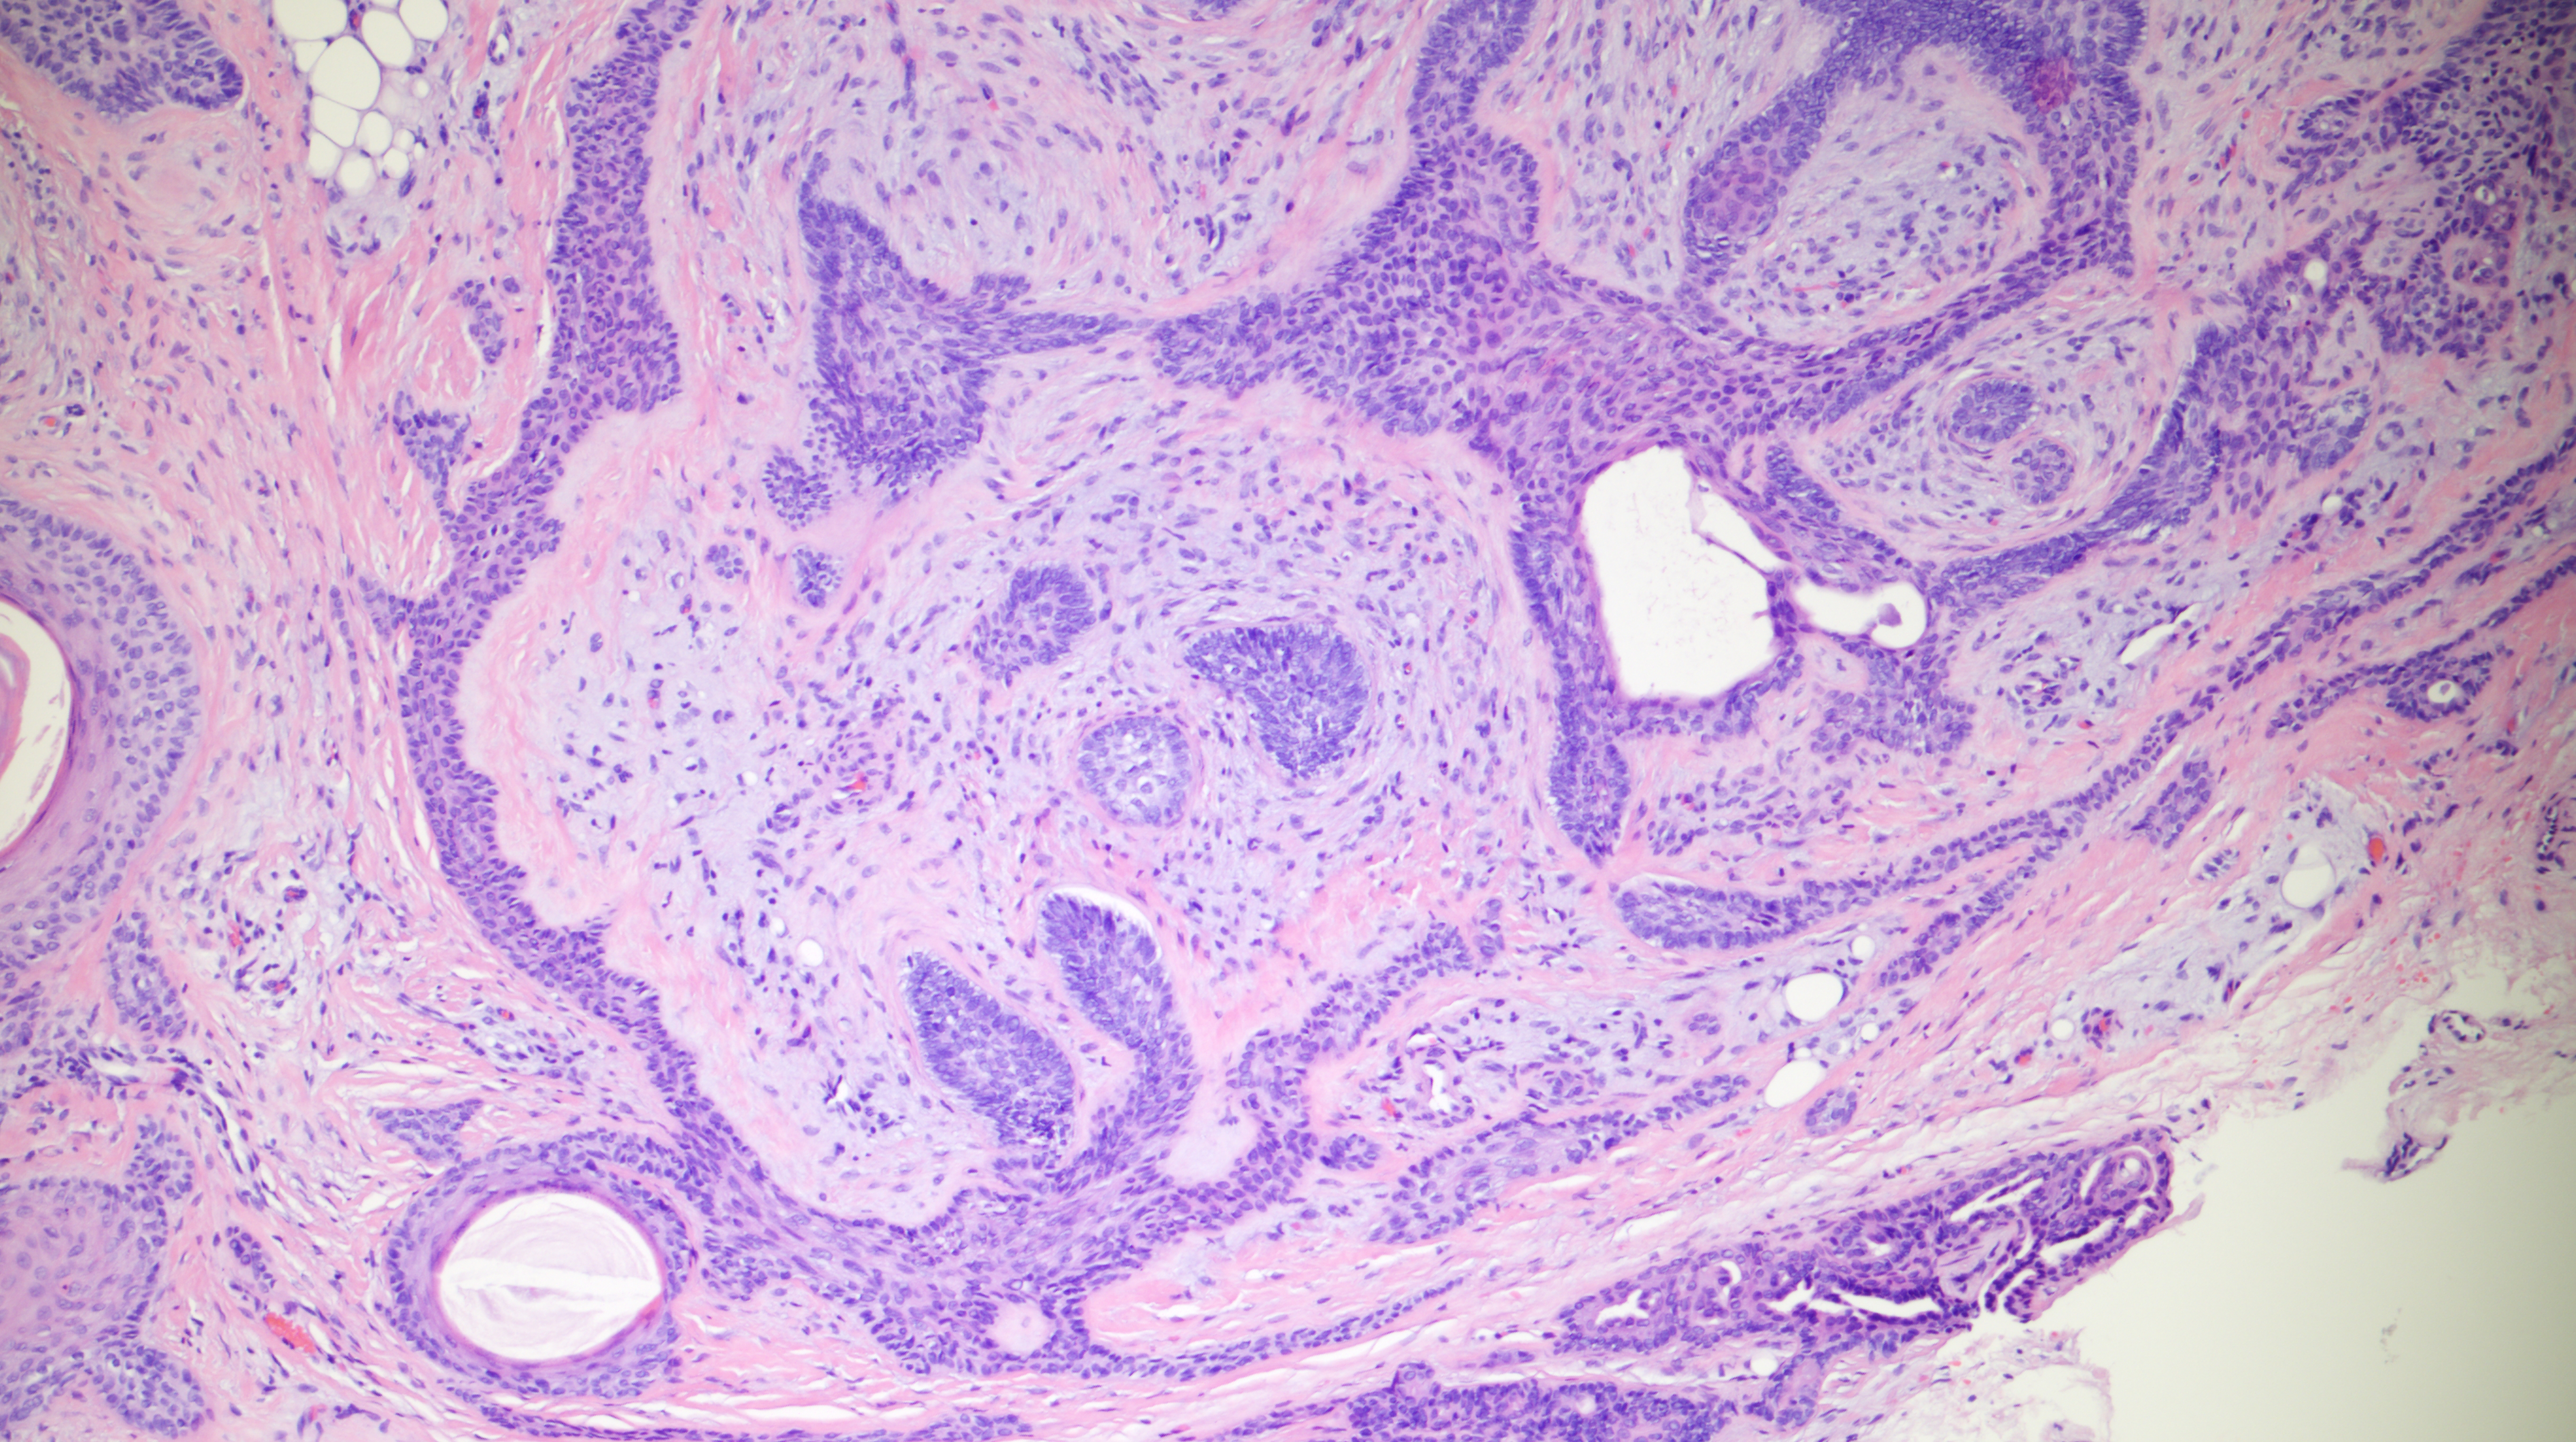

60-year-old man with an upper lip nodule.